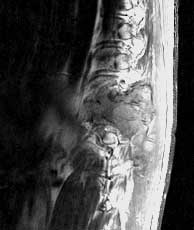

T1 sagittals pre-gad

Findings:

Extensive soft tissue mass in the left paraspinal and chest wall region with mixed signal.